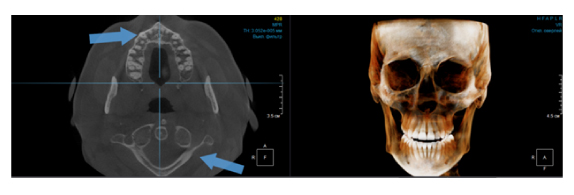

Когда мы отправляем пациента на проведение рентгенологического исследования, то подвергаем его определенному риску. Именно это нужно осознавать, так как в радиологии нет минимально безопасной дозы, поэтому любое назначение должно быть обоснованным. В связи с этим поле обзора является достаточно принципиальным параметром. Если вы врач-терапевт, занимающийся эндодонтией или ортопед, который решил оценить состояние зубов перед протезированием, то вы должны понимать, что проведение исследования с полем обзора 10x10 см будет гораздо информативнее нежели большие снимки (18x16 см и выше). В первую очередь это связано с размером вокселя, о нём я напишу чуть ниже, а второе это то, что вам придется увеличивать изображение по каждому корневому каналу, и от этого вы будете терять в качестве снимка (рис. 1). И ситуация наоборот, если вы ортодонт, то чтобы использовать весь диагностический потенциал, а также возможность загрузить данные для расчёта 3D цефалометрии, то вам нужны снимки, захватывающие весь лицевой отдел черепа. Таким образом, дентальный томограф должен обладать возможностью проведения исследований с разным FOV, обеспечивая нужды всех специалистов. Если ваша клиника базируется на терапевтическом, хирургическом и ортопедическом приёме, то на мой взгляд, можно рассмотреть дентальные томографы с полем обзора 10x10 см или 16x10 см. Последний больше актуален для тех, кто работает с ВНЧС, так как антропометрически в 16 см даже у брахицефалов сустав должен попадать.  Если в клинике есть ортодонтическое направление, функциональная стоматология, ЛОР-практика или ЧЛХ, то, безусловно, вышепредставленные снимки не будут отражать всех данных, которые необходимы для диагностики и планирования лечения. Здесь лучше рассмотреть конусно-лучевые компьютерные томографы с зоной сканирования 18x16 или 20x20 см. Особо стоит отметить понятие «сшивки». Есть дентальные томографы, которые делают один цельный снимок размерами, которые описаны выше, а есть аппараты, которым нужно провести две экспозиции и сшить изображения вместе, чтобы получился необходимый объём исследования. Как правило, вторые томографы чуть дешевле, но всё зависит от того, насколько вам нужна максимальная точность исследования. Если при сшивке челюсти и зубы, как правило, совмещаются практически идеально, то на уровне позвоночного столба происходит наслоение тканей и от него уже не избавиться (рис. 2). Второй отрицательный момент – это износ оборудования, логично, что он будет быстрее, так что экономия средств — это ещё спорный вопрос.

Рис. 2. Левый снимок представлен исследованием 20x20 см единым изображением. Стрелками показаны чёткость канально-корневой системы зуба, а также позвоночника. Правый снимок представлен исследованием 16x15 см с функцией сшивки. Стрелками обозначены чёткость зуба, но двойной контур позвоночника.